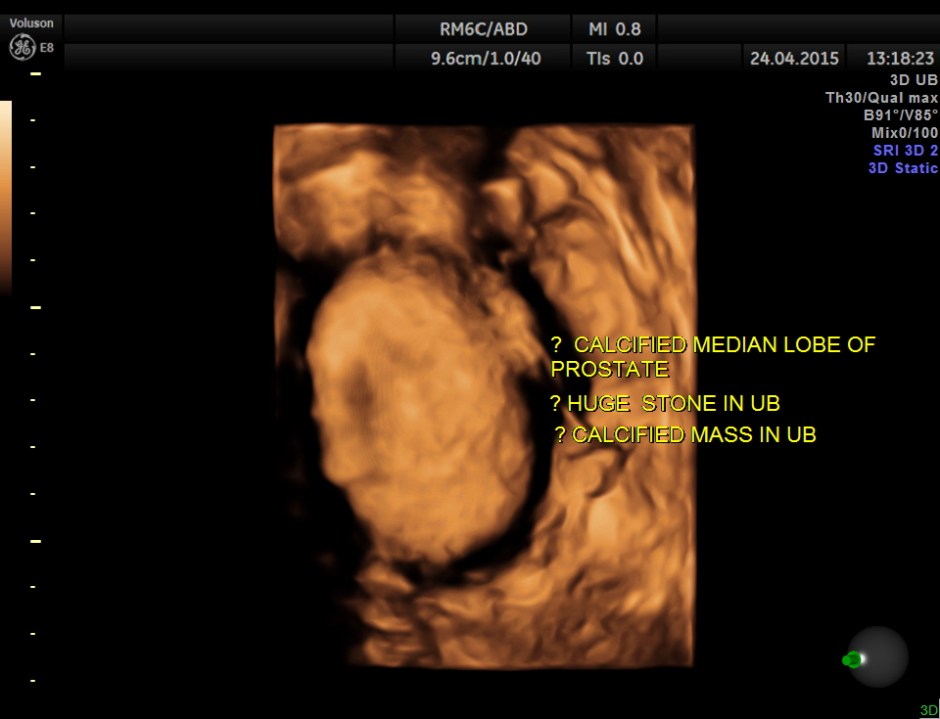

A large calcification in the urinary bladder – ? large urinary bladder stone , calcified median lobe of the prostate, or a calcified mass within the bladder .

3D tweaking looks more like a large stone.